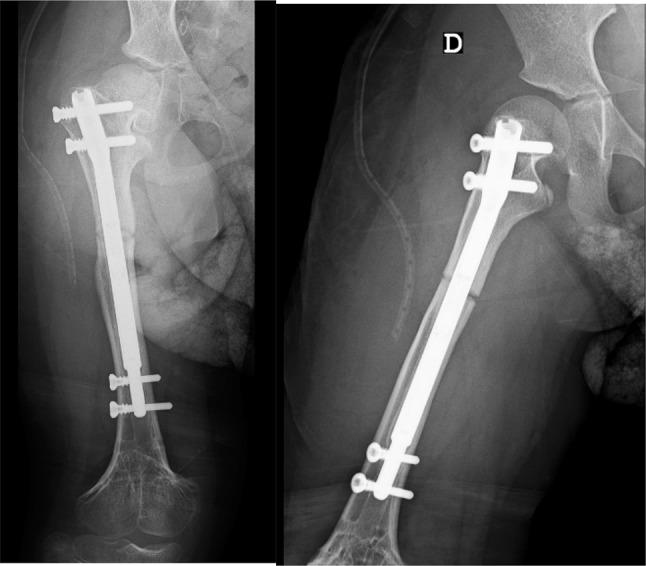

The authors present a case in which the limb lengthening has been performed in consecutive lengthening periods using the same nail. The nail was extended and retracted by altering the settings on the external remote control as well as accurately setting the rate of distraction.

After two consecutive femoral lengthening with the same PRECICE nail, the patient no longer has a significant lower limb length discrepancy and patient satisfaction was high. During this clinical case, we were not confronted with any type of complications.

作者呈现了一个病例,其中使用同一根钉子在连续的延长阶段进行肢体延长。通过改变外部遥控器的设置以及精确设定牵张速率来使钉子延长和回缩。

使用同一根PRECICE钉子连续两次进行股骨延长后,患者双下肢长度差异不再显著,患者满意度较高。在这个临床病例过程中,我们未遇到任何类型的并发症。